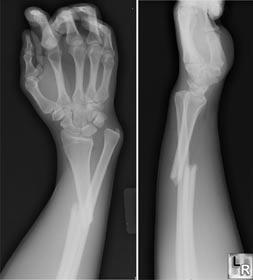

拍片了.错位.. 然后.不知道怎么办.?除了手术.还有什么更好的方法治疗了.?曾经用中药敷过一阵子.然后发痒,发痛.受不了了.医生就叫拆下..现在手已经严重歪斜.请问,有更好的答案么.?拜托了!

如果线行骨折且对位良好就可以采用石膏外固定,如果粉碎性骨折或者错位较大,就需采取手术切开复位内固定。